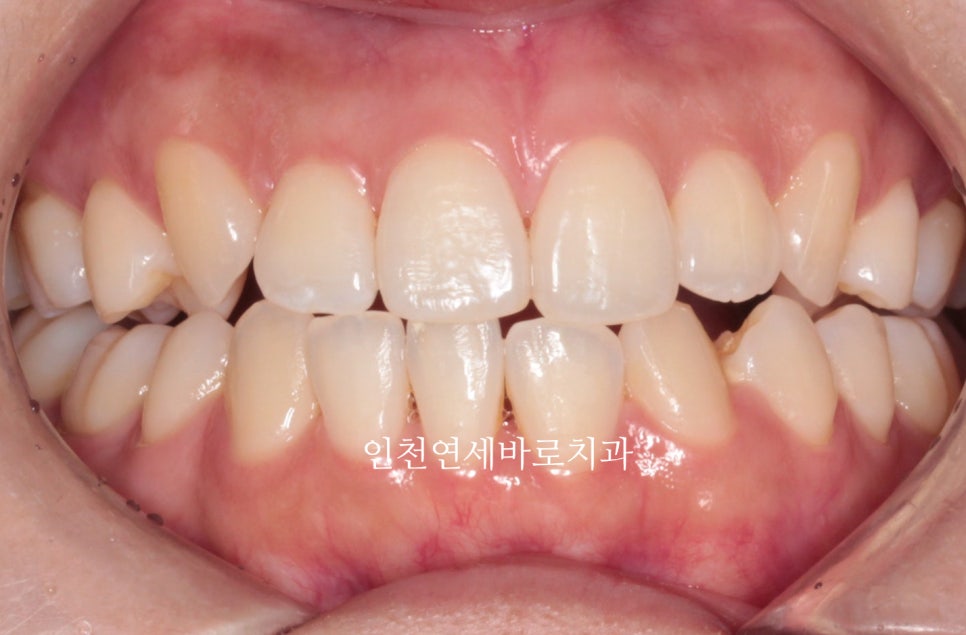

선천적결손치아가 있던 환자분이며, 웃을때 사진을 보면 약간의 비대칭도 관찰됩니다.

아래 앞니가 없다보니 중심선도 안맞고, 아래 치아의 사이즈도 양쪽이 다름을 알 수 있습니다.

비대칭이 있다보니 위쪽 치아가 전체적으로 기울어져 있는것도 확인됩니다.